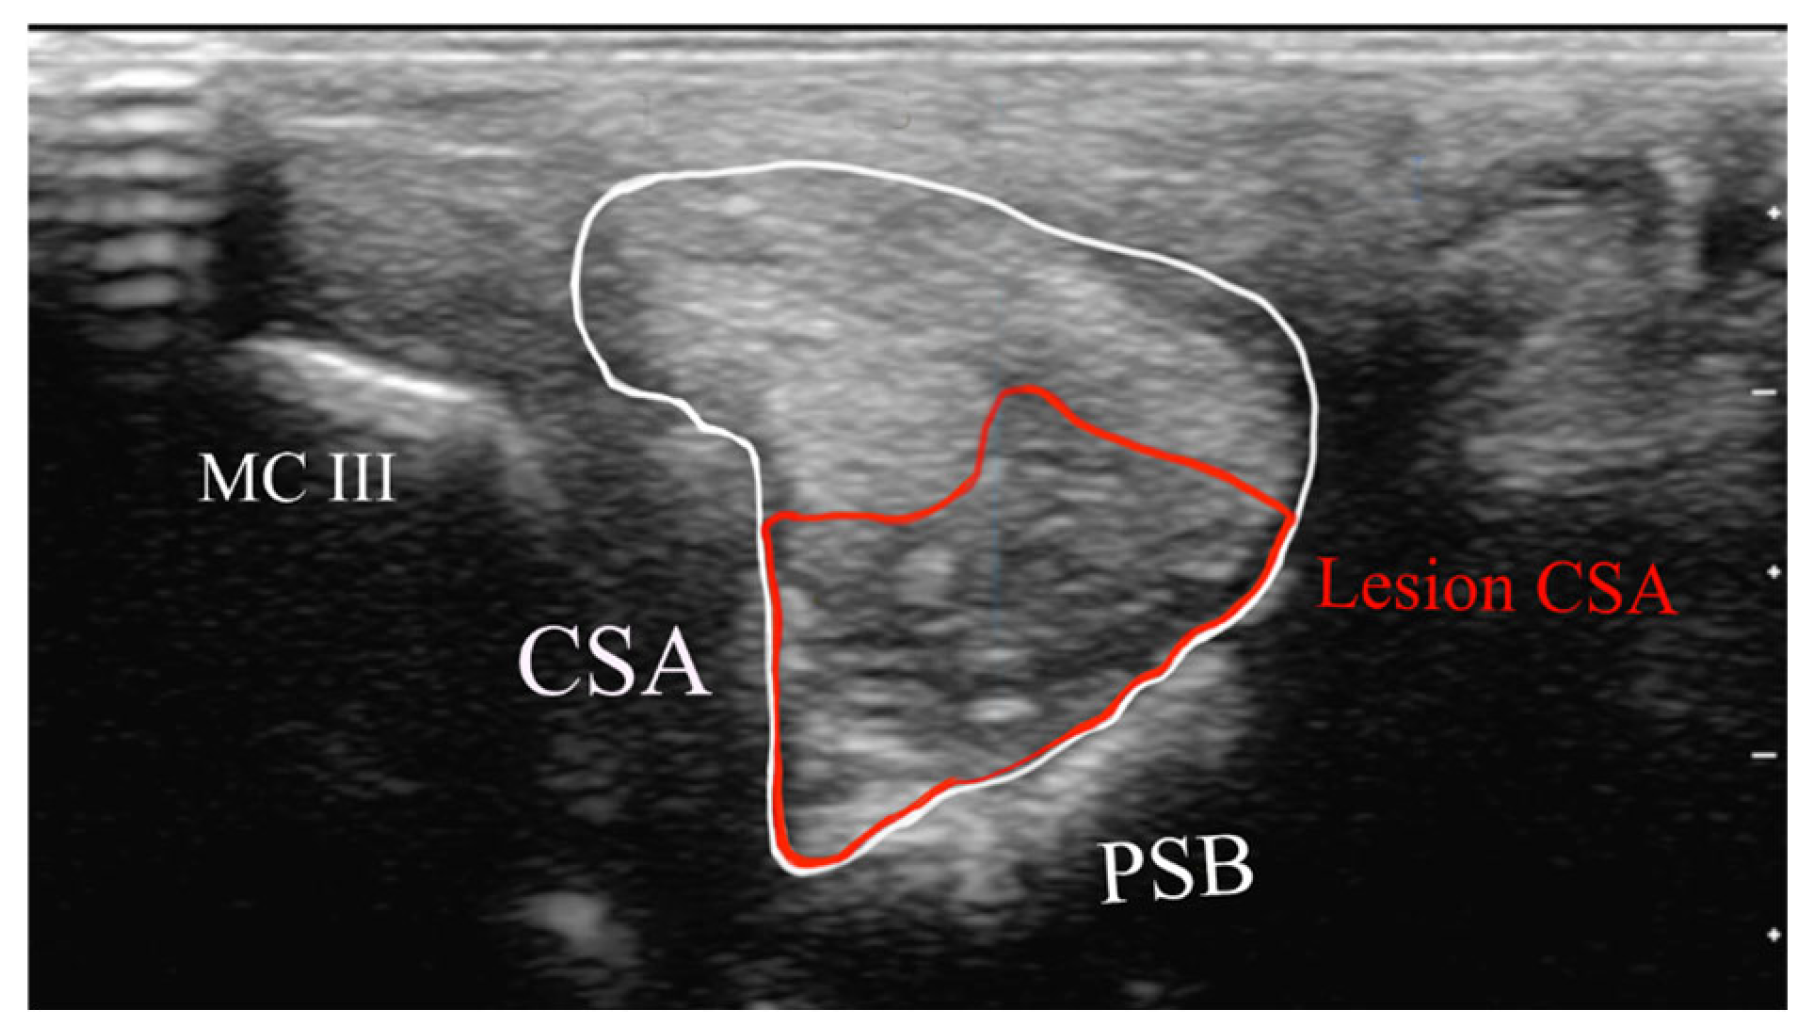

2.4.1. Classification of Ultrasonographic Lesions

- Cross-sectional area of the SL branch (cm2);

- Lesion CSA (cm2).